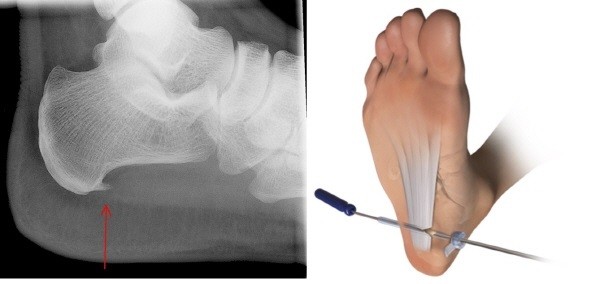

수술적 치료

만약 비수술적 치료가 효과를 나타내지 않는 경우, 수술적인 접근이 고려됩니다. 이러한 수술 중 하나는 족저근막을 늘려주는 것이며, 최근에는 관절경을 이용하여 족저근막 절개술을 시행하는 경우도 있습니다. 이러한 수술적 치료는 환자의 상태와 전문의의 의견을 기반으로 결정됩니다.

족저근막염의 치료에 대한 결정은 환자의 개별적인 상황과 증상에 따라 다를 수 있으므로 의료 전문가와 상담하는 것이 중요합니다.